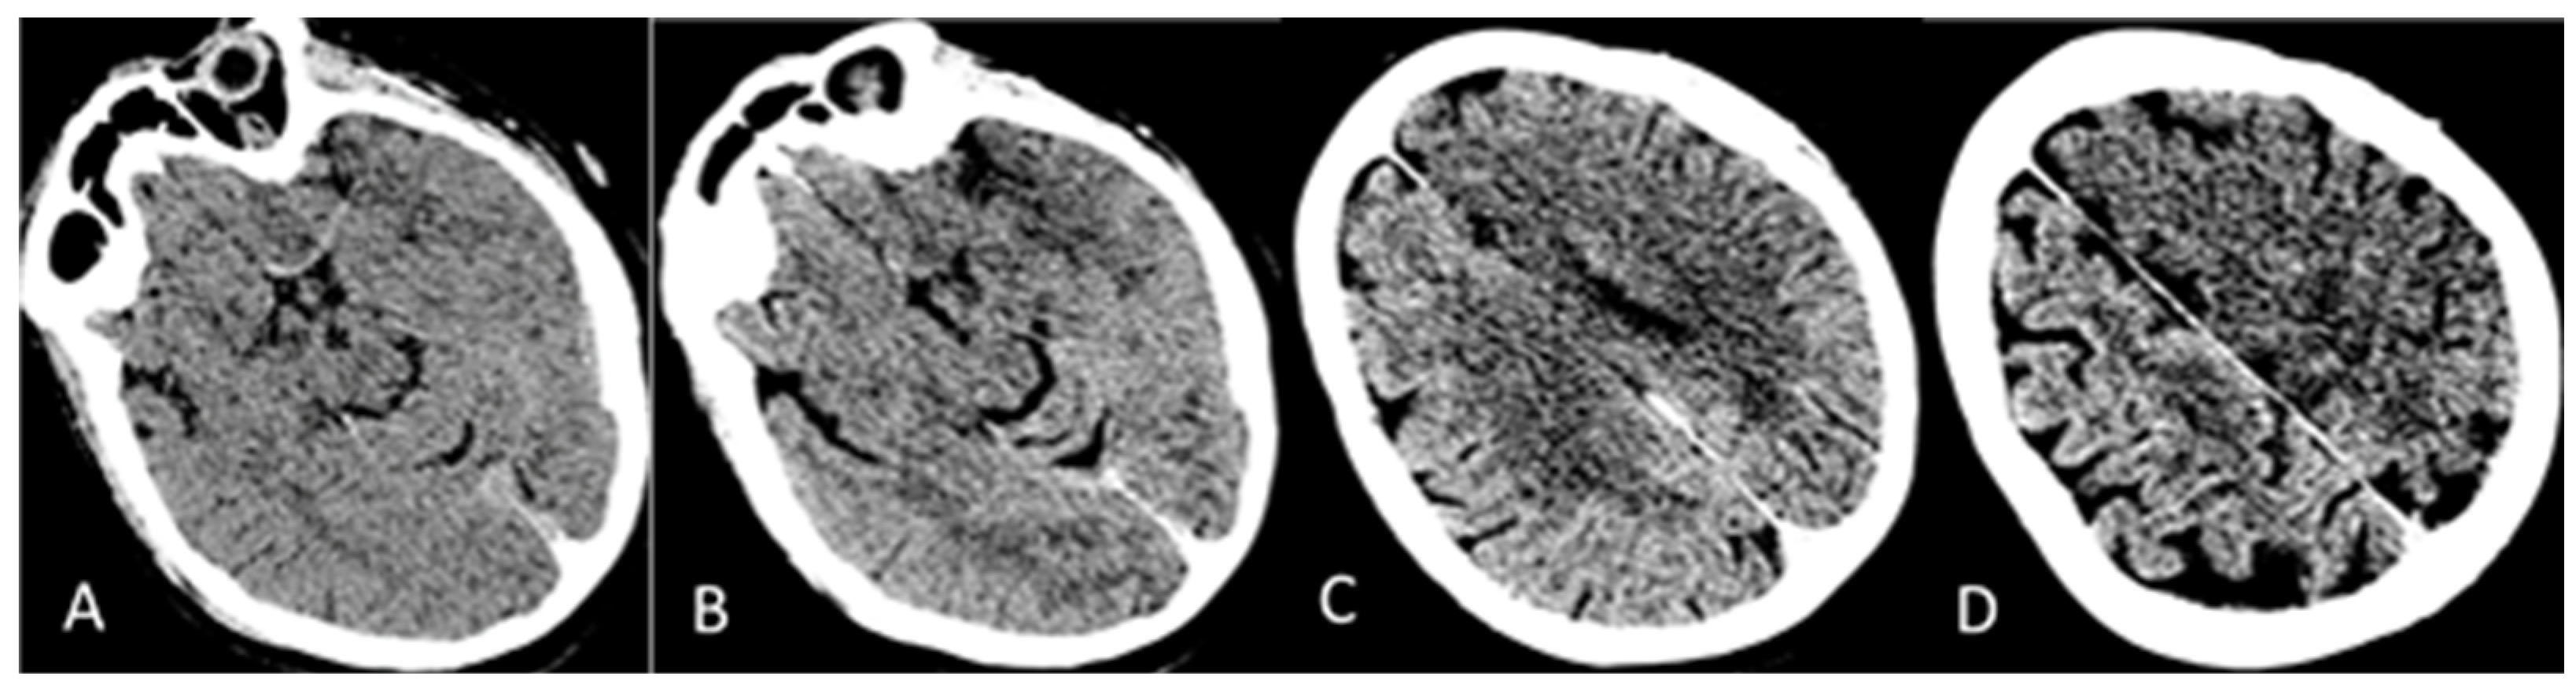

2. Detailed Case Description